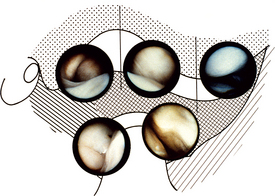

The joint can be examined by direct vision, but it is more common to attach a video camera to the scope and to display what is seen on a television monitor (Fig. 17.4).

image

Fig. 17.4 Views of the TMJ obtained through the arthroscope. Top left = upper posterior synovial pouch; top middle = intermediate space showing disc below; top right = upper anterior synovial recess; bottom left = lower posterior synovial pouch; bottom right = lower anterior synovial pouch.

(courtesy of Dr K.-I. Murakami and Harcourt Brace Publishers)

With the simplest of equipment the joint can be inspected, usually starting with the posterior recess, looking at the position of the disc, the condition of the posterior attachment tissues and the synovium on the medial aspect of the joint. The scope is then swept anteriorly over the top of the disc to look at the anterior parts of the joint. By inspection alone it is possible to detect disc displacement, adhesions, degenerative changes in the disc and cartilage over the glenoid fossa and articular eminence and synovial inflammation. It is possible, if adhesions are detected, to replace the blunt-ended trocar and sweep around within the joint to break them down. The joint must be thoroughly irrigated at the end of the procedure and many surgeons will finally instil a steroid before leaving the joint. It is often necessary to place one suture in the skin wound.